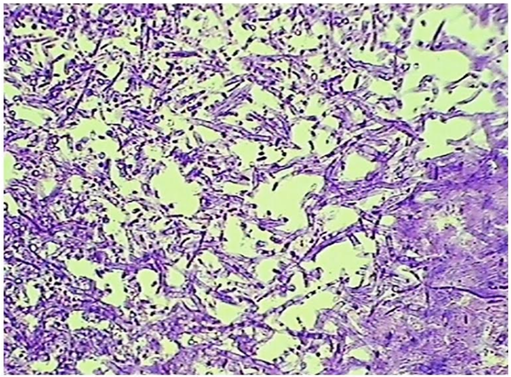

Acoustic immittance was normal. Intravenous Gadolinium (IV-Gd)1.5 T MRI showed the features of labyrinthitis in the left ear (Figure 1).

Figure 1 Findings on the IV-Gd1.5 T MRI.

(A)White arrow indicated the location of the middle ear and the red arrow pointed to the vestibular of the inner ear, both structures in the left side showing higher density in than those in the right ones. (B) White arrow pointed to the middle ear and the red arrow to the location of the base turn of cochlea, indicating both structures showing higher density in the left side than those in the right ones.